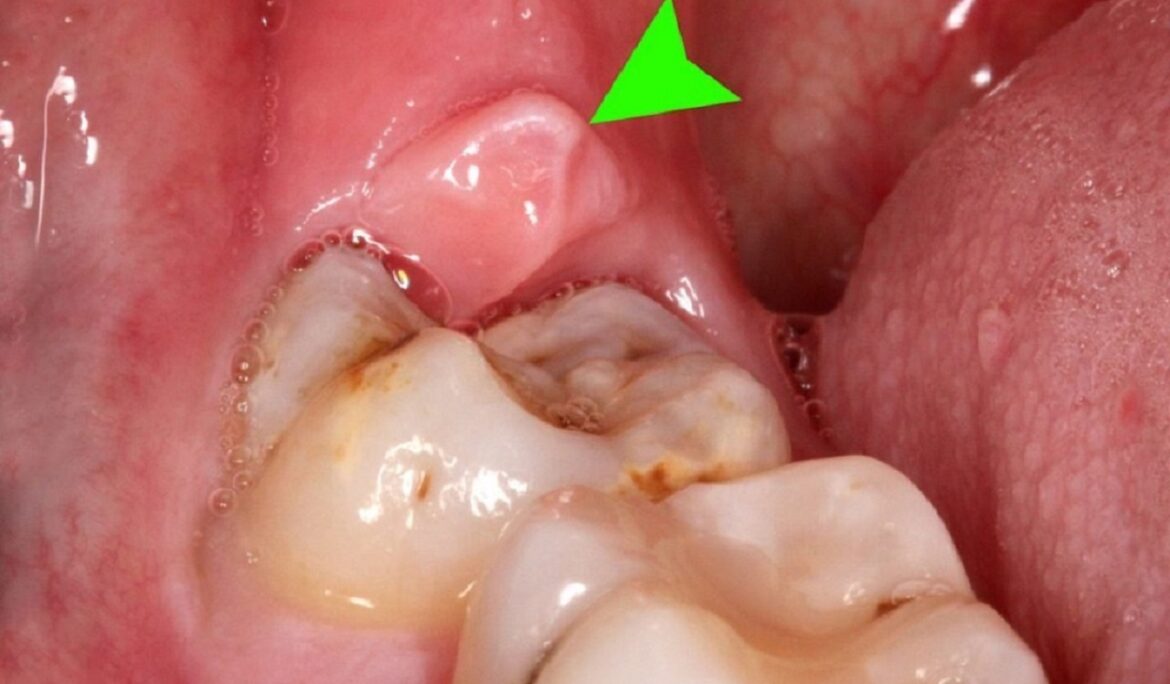

Mọc răng khôn

Mọc răng khôn, đặc biệt là khi răng khôn mọc lệch hoặc mọc ngầm, là một trong những nguyên nhân phổ biến gây sưng, đau và tổn thương nướu. Quá trình này thường xảy ra trong độ tuổi trưởng thành. Vì thế có thể gây ra nhiều vấn đề nếu không được chăm sóc đúng cách. Răng khôn mọc không đúng vị trí có thể gây áp lực lên các răng lân cận. Theo thời gian có thể làm tổn thương nướu, khiến nướu bị sưng và dễ bị viêm.

Những người bị mọc răng khôn thường cảm thấy đau nhức. Đồng thời sẽ luôn gặp khó khăn trong việc ăn uống và giao tiếp. Trong một số trường hợp, nếu không được can thiệp kịp thời, tình trạng viêm có thể lan rộng. Từ đó gây ra các biến chứng nghiêm trọng như áp-xe răng hoặc nhiễm trùng. Việc thăm khám nha khoa và điều trị kịp thời là rất quan trọng. Thông qua đó giảm thiểu những ảnh hưởng của việc mọc răng khôn.